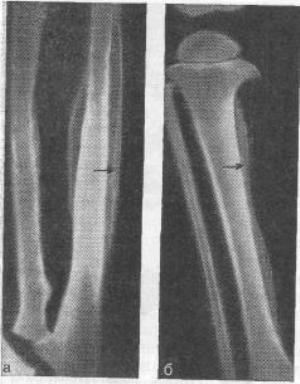

У некоторых больных эта патология возникает резко и не имеет связи ни с одной болезнью. При рентгенисследовании излюбленных мест локализации на конечностях, а также других поврежденных областей тела наблюдается симметричное утолщение диафизарной части, которое образовалось вследствие ровных, гладких периостальных наслаиваний. В последующем последние более уплотняются и соединяются с корковым слоем.

Другое название патологического состояния — болезнь Камурати-Энгельманна, которая была выявлена в первой половине двадцатом веке врачом Камурати (Италия) и хирургом Эгельманном (Австрия). Она входит в группу генетических патологических проявлений, передача которых осуществляется по аутосомно-доминантному виду. Патологические явления формируются в диафизарных зонах бедренных, плечевых и большеберцовой костей. И как исключение возможно повреждение иных костей.